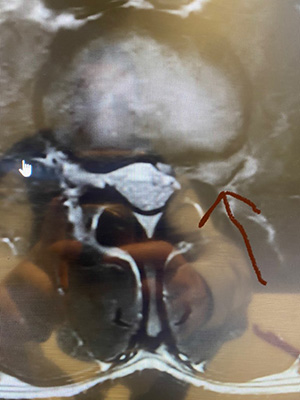

We recently had one such case of this uncommon occurrence in a 38-year-old bodybuilder who, after a particularly rigorous set of exercises over a month period, began having severe pain, numbness, and weakness into the left thigh region radiating from his back into his left knee.  He came in to see us at the Center for Musculoskeletal Disorders, and had an immediate MRI ordered showing a very large L2-3 far lateral disc herniation.  We attempted an epidural steroid injection to give him some relief, with the understanding that it may not give him the necessary long-term comfort and resolution

Indeed, it did reduce the symptoms, but not enough for this very active gentleman.  So…earlier this month he was brought to the Bergenfield Surgical Center and, using a microscopic tubular approach and a small, 1.8 cm incision on his back, a tube was docked onto his L2-3 left lateral space and the herniated disc, using microscopic assistance, was removed.  The patient left the surgery center approximately an hour and one-half after the procedure, pain reduced and the wounds healing very well!!  Photos are enclosed.